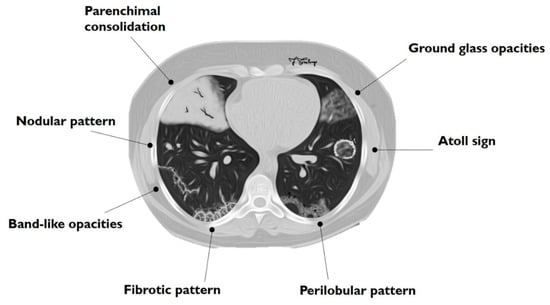

Figure 1. Schematic drawing of main imaging patterns of cryptogenic organizing pneumonia (COP).

The main HRCT findings in OP include: consolidation, ground-glass opacity (GGO), perilobular opacity, reversed halo opacity, nodules or masses, parenchymal bands, bronchial wall thickening, bronchial dilatation, mediastinal lymphadenopathy and pleural effusion [24,25]. The radiological features of COP can be divided into two main groups: typical and atypical patterns (Table 1, Figure 1). Typical pattern consists of multiple air spaces-opacities or peripheral consolidations with air bronchogram; as reported by Polverosi et al. [22], these consolidations may be limited by GGOs. According to many papers reported in literature, an atypical pattern includes: solitary or multiple nodules or masses (that constitute the nodular pattern), infiltrative opacities (infiltrative COP), atoll sign, bronchocentric lesions, linear and band-like opacities, a crazy paving pattern and progressive fibrosis [20,22,24,26].